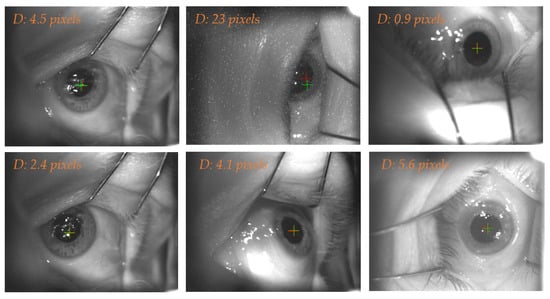

This network received the original image as input and predicted the eye position, resulting in the eye center coordinates. To evaluate its performance, we computed the Euclidean distance between the predicted eye center and the ground truth label. For the 57 frames included in the test set, median (IQR) Euclidean distance, was 3.05 (4.14) pixels. Figure 6 illustrates some exemplary cases.

Figure 6.

The crosses identify the eye center computed from the manually labelled eye (red) and the ROI U-Net predictions (green).